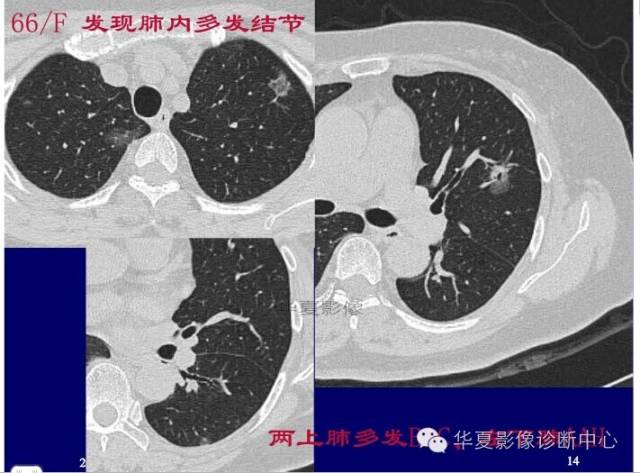

第一步:判断是否GGO

第二步:判断是否肿瘤

第三步:看边缘及内部征象

磨玻璃结节良恶性影像分析策略 混合型,边界清楚、分叶征,考虑肺癌

边界清楚,分叶征,空泡征